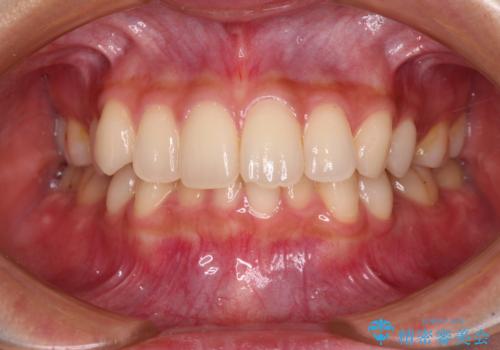

前歯をさげたい 歯を抜かずに マウスピース矯正で治したい

[ インビザライン矯正 ]マイクロインプラント用いた大きな遠心移動

担当医 大元洋佑